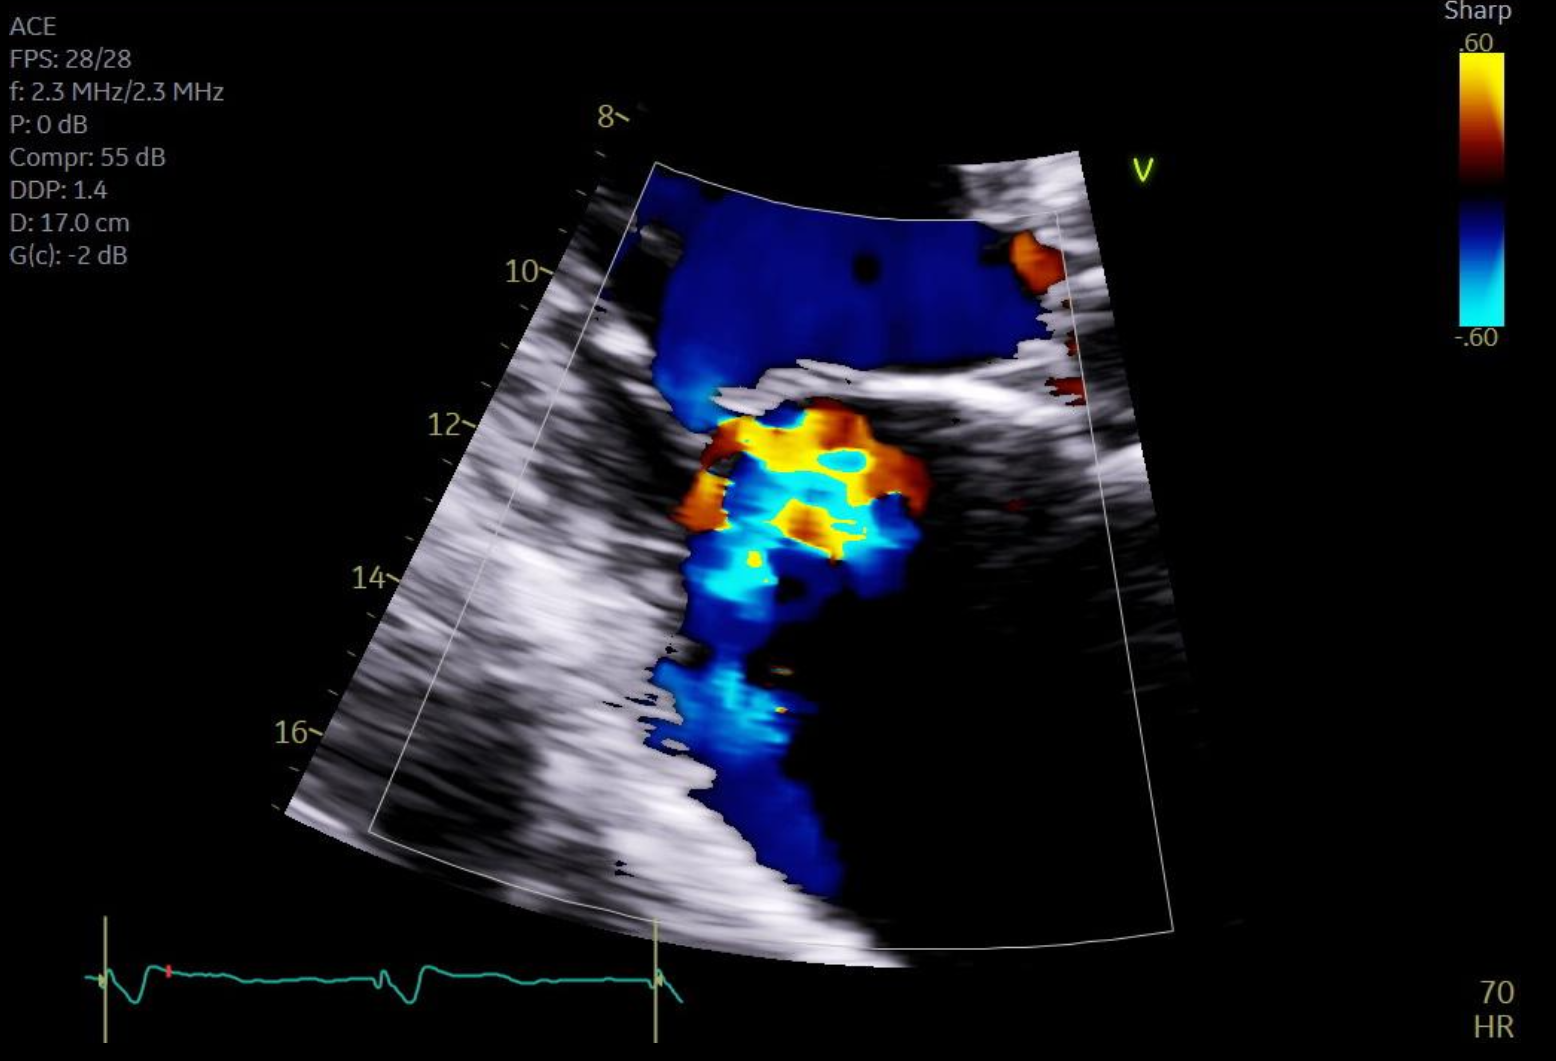

A mitral regurgitation echo is often the first step in diagnosis. This test evaluates regurgitant volume, jet direction, chamber size, and overall cardiac function. Early-stage cases like trace mitral valve regurgitation or mild to moderate mitral valve regurgitation are typically found during routine echocardiography.

For more precise visualization, TEE—especially 3D TEE mitral valve imaging—offers enhanced resolution. This includes the bicommissural view TEE, short axis mitral valve plane, and the ability to assess specific leaflet segments such as A1, A2, A3. These views help differentiate between types of regurgitation and identify causes such as mitral valve prolapse or leaflet restriction.

Other echocardiographic parameters like mitral valve area pressure half-time, DVI mitral valve, and flow reversal are used to quantify severity and guide next steps. These tools are also helpful in identifying conditions like nonrheumatic mitral valve insufficiency and mild mitral valve regurgitation—often asymptomatic but clinically significant over time.

Imaging for Repair Planning